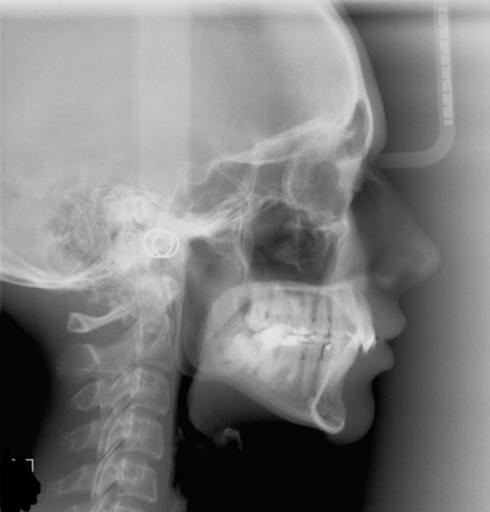

can i have a second jaw surgery to make jaw short

I had a surgery about a year ago I had a underbite problem my upper jaw was move foward and my lower jaw move back i have a perfect bite now my teeth fit together and everything the problem is that I still don\'t like how my lower jaw is still pretty big it makes my face look big I always had a low self esteem about my lower jaw being pretty big and I was just wondering if I can get a second jaw surgery to make my jaw short